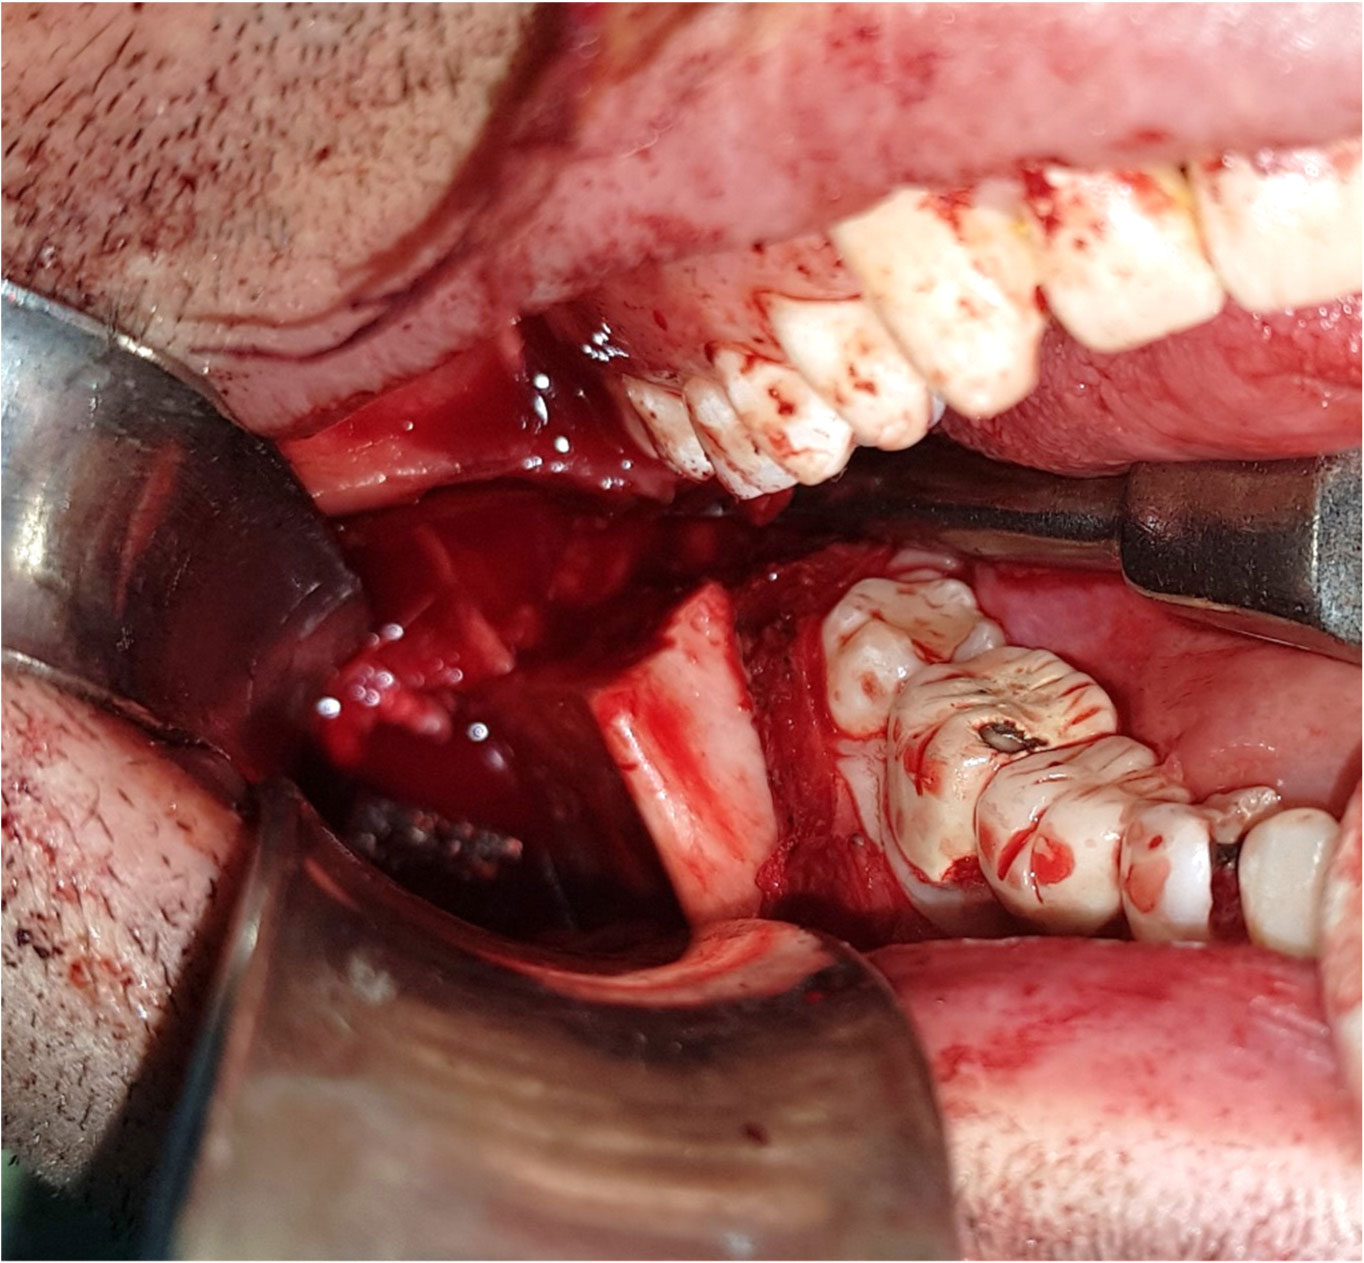

• The case of a 27-year-old male with a destructive aneurysmal bone cyst of the right mandibular condyle, coronoid process and ascending ramus is presented. Surgery revealed an eggshell-thin, partly perforated cortices. Intraoral approach was used for a complete resection of mandibular condyle, coronoid process and affected ascending mandibular ramus. Curettage of the adjacent soft tissues performed; no extra oral incision was used. In this case following resection, the defect was primarily reconstructed with prefabricated reconstruction plate with condylar head to maintain functional mandibular ramus height, avoid malocclusion and asymmetry. Post-operative examination and radiographic images revealed good symmetry and perfect occlusion as well as almost normal mandibular function. Intraoral approach can be used to access to the mandibular condyle region and ascending ramus with no risk to facial nerve and skin scar so cosmetically more favorable.